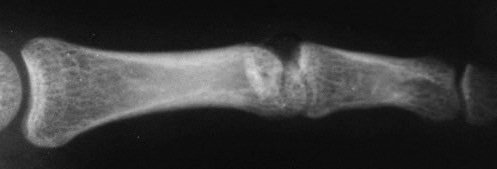

Initial films. Radial condyle is missing here..

Click for larger image

There it is!